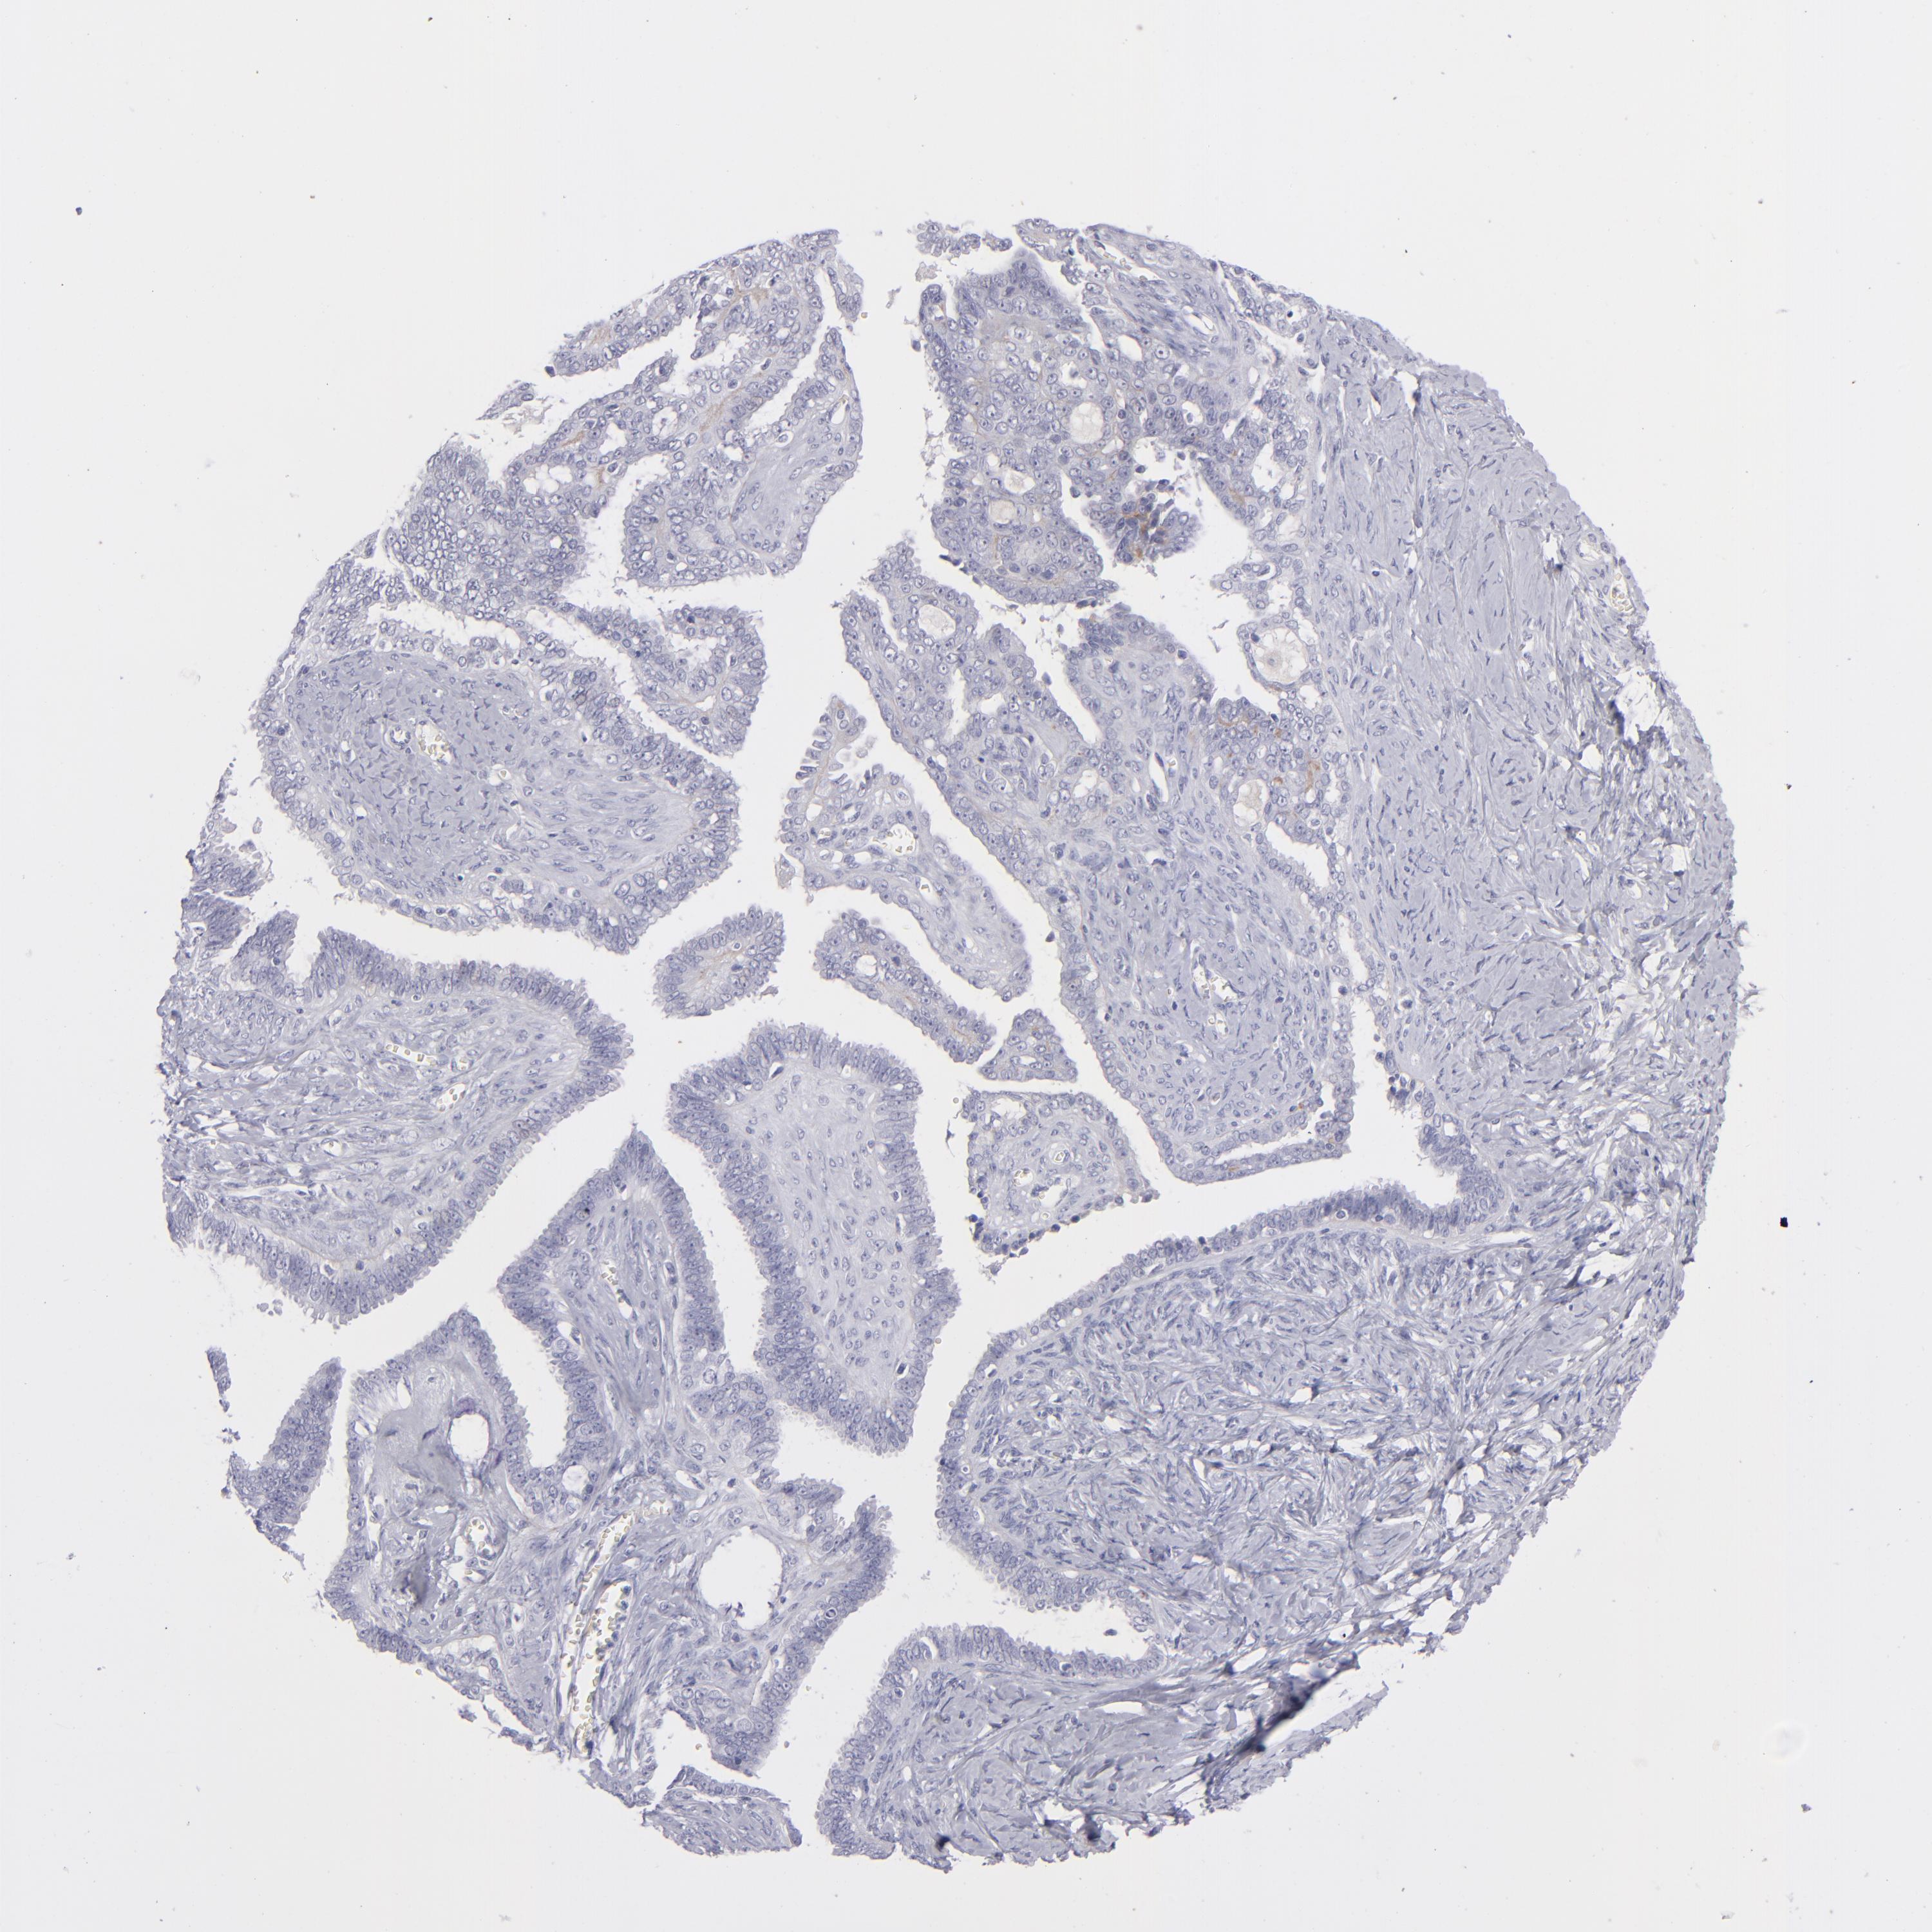

OVARIAN CANCER - Protein expressioni

A mouse-over function shows sample information and annotation data. Click on an image to view it in a full screen mode. Samples can be filtered based on level of antibody staining by selecting one or several of the following categories: high, medium, low and not detected. The assay and annotation is described here.

Note that samples used for immunohistochemistry by the Human Protein Atlas do not correspond to samples in the TCGA dataset.

Antibody stainingi

Antibody staining in the annotated cell types in the current human tissue is reported as not detected, low, medium, or high, based on conventional immunohistochemistry profiling in selected tissues. This score is based on the combination of the staining intensity and fraction of stained cells.

Each image is clickable and will lead to virtual microscopy that enables deeper exploration of all samples and also displays staining intensity scores, fraction scores and subcellular localization as well as patient and tissue information for each sample.

Antibody HPA036348

Antibody HPA036349

Antibody CAB002422

Antibody CAB005258

Cystadenocarcinoma, serous, NOS

Carcinoma, NOS

Cystadenocarcinoma, mucinous, NOS

Carcinoma, endometroid